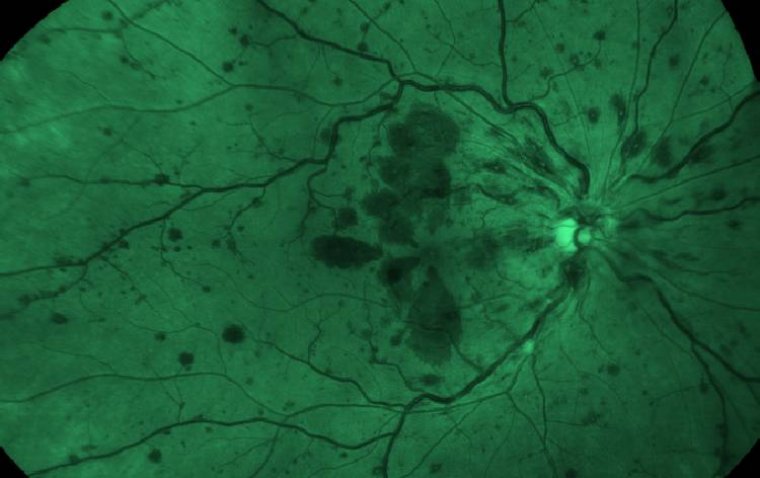

Как пояснил доктор Ю, в центре внимания исследователей находится роговица. Ученые стремились понять, почему пациенты с диабетом более восприимчивы к кератиту (инфекции роговицы), почему заболевание прогрессирует быстрее и почему они более устойчивы к лечению. Вероятность развития инфекций роговицы у диабетиков примерно на 30% выше.

У пациентов с диабетом наблюдается более высокая частота инфекций, большая тяжесть заболевания и повышенная устойчивость к некоторым видам лечения, что приводит к быстрому прогрессированию микробного кератита. Доктор Ю отметил, что в ходе работы были получены доказательства большей восприимчивости мышей к инфекциям роговицы. Анализ образцов инфицированных роговиц мышей со сходной степенью тяжести, включая изучение последовательностей РНК, позволил сравнить прогрессирование инфекции и идентифицировать задействованные пути (биологические процессы). Сопоставление нормальных и диабетических путей открыло возможности для поиска потенциальных методов лечения.